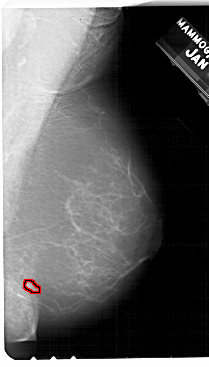

A_1943_1.LEFT_CC

LEFT_CC LINES 5491 PIXELS_PER_LINE 3226 BITS_PER_PIXEL 12 RESOLUTION 43.5 NON_OVERLAY

FILE: A_1943_1.RIGHT_CC.OVERLAY

TOTAL_ABNORMALITIES 1

ABNORMALITY 1

LESION_TYPE MASS SHAPE LOBULATED MARGINS ILL_DEFINED

ASSESSMENT 4

SUBTLETY 3

PATHOLOGY BENIGN

TOTAL_OUTLINES 1

BOUNDARY